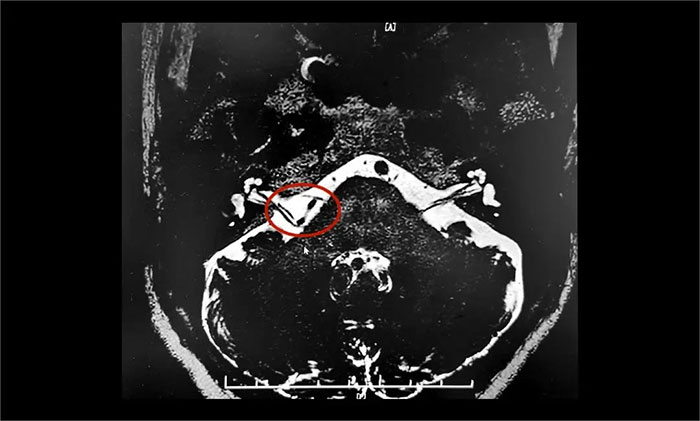

為進(jìn)一步治療,王阿姨在家人陪伴下慕名來(lái)到上海藍(lán)十字腦科醫(yī)院。入院后,楊忠旭教授團(tuán)隊(duì)認(rèn)真評(píng)估了王阿姨面肌痙攣發(fā)生的頻率、強(qiáng)度和持續(xù)時(shí)間,并完善了核磁顱神經(jīng)檢查。面神經(jīng)MRTA+增強(qiáng)顯示:右側(cè)面神經(jīng)與周圍小血管關(guān)系密切。

▲ 右側(cè)面神經(jīng)與周圍小血管關(guān)系密切